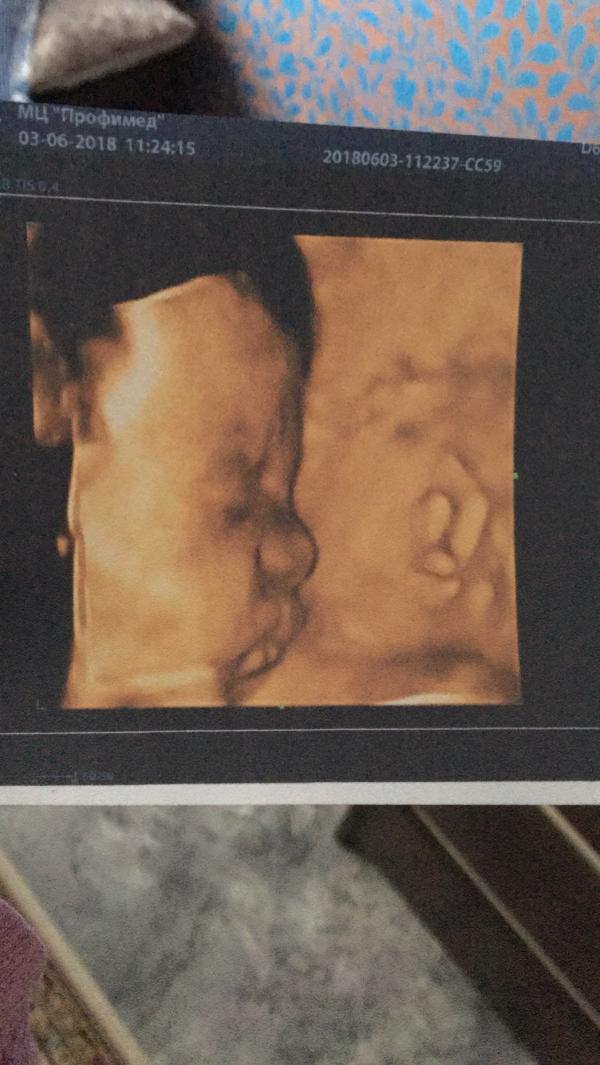

Доча до сих пор в тазовом предлежании🙄 надеюсь перевернётся, все твердят что ещё рано паниковать, мол ещё есть время, а я переживаю😐

P.s. Наш вес 1670 (+/- 200 гр)

Ровно 30 недель